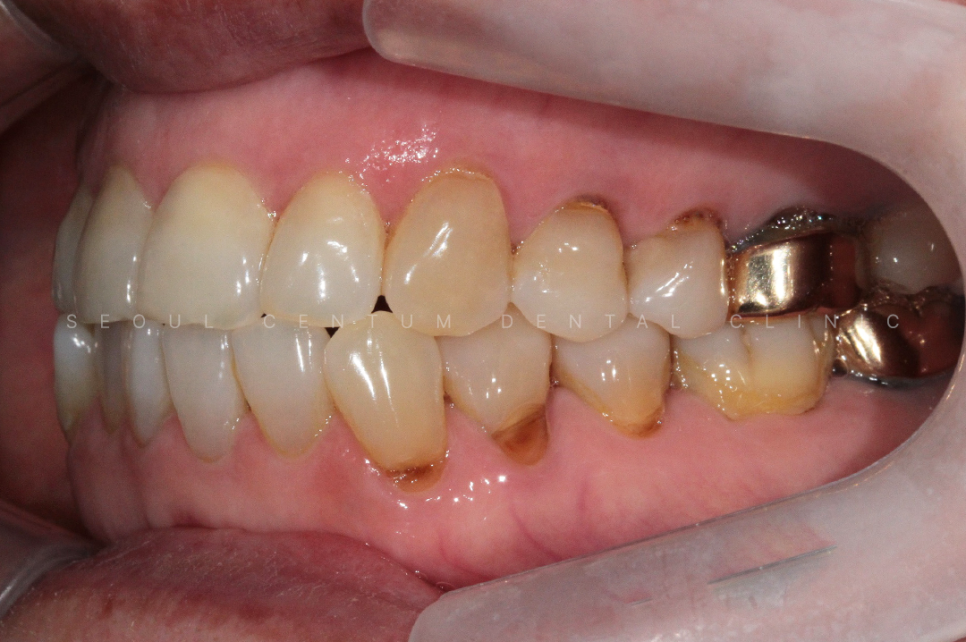

아래 사진은 실제 서울센텀치과에

치경부마모증이 뭔지 모르는 상태로

내원하셔서 치료를 하게 된 케이스인데요.

60대 여성으로 동네에 치과에 스케일링을

오랫만에 하러 갔다가

치아가 파였다는 말을 듣고

거울을 보고나니 치아가 보기 싫어져서

라는 이유로 내원을 하셨어요.

실제 육안으로 봤을 때도 크게

치경부마모증이 진행된 부분이 많았고

당일에 바로 진행을 하게 되었습니다.

크게 진행이 된 8개의 치아를 진행하기로 했고

강도가 강한 레진으로 진행해 오래

유지를 잘 해보시기로 이야기가 되어

레진으로 진행을 했습니다.